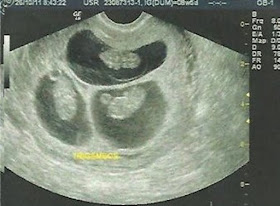

Li em um blog, esses dias, sobre uma mãe ao receber a notícia de que estava grávida de trigêmeos, suas reações foram do espanto ao pânico em fração de segundos, quase entrando em estado de choque.

Penso aqui, que não há forma para dizer que você esta grávida de um, dois, ou três filhos. Um médico tem que dizer o que vê no exame; nós quando engravidamos temos que nos preparar para as novidades, daí para frente teremos sempre novidades, nada será igual. Cada filho nos dará uma gravidez diferente, inusitada.